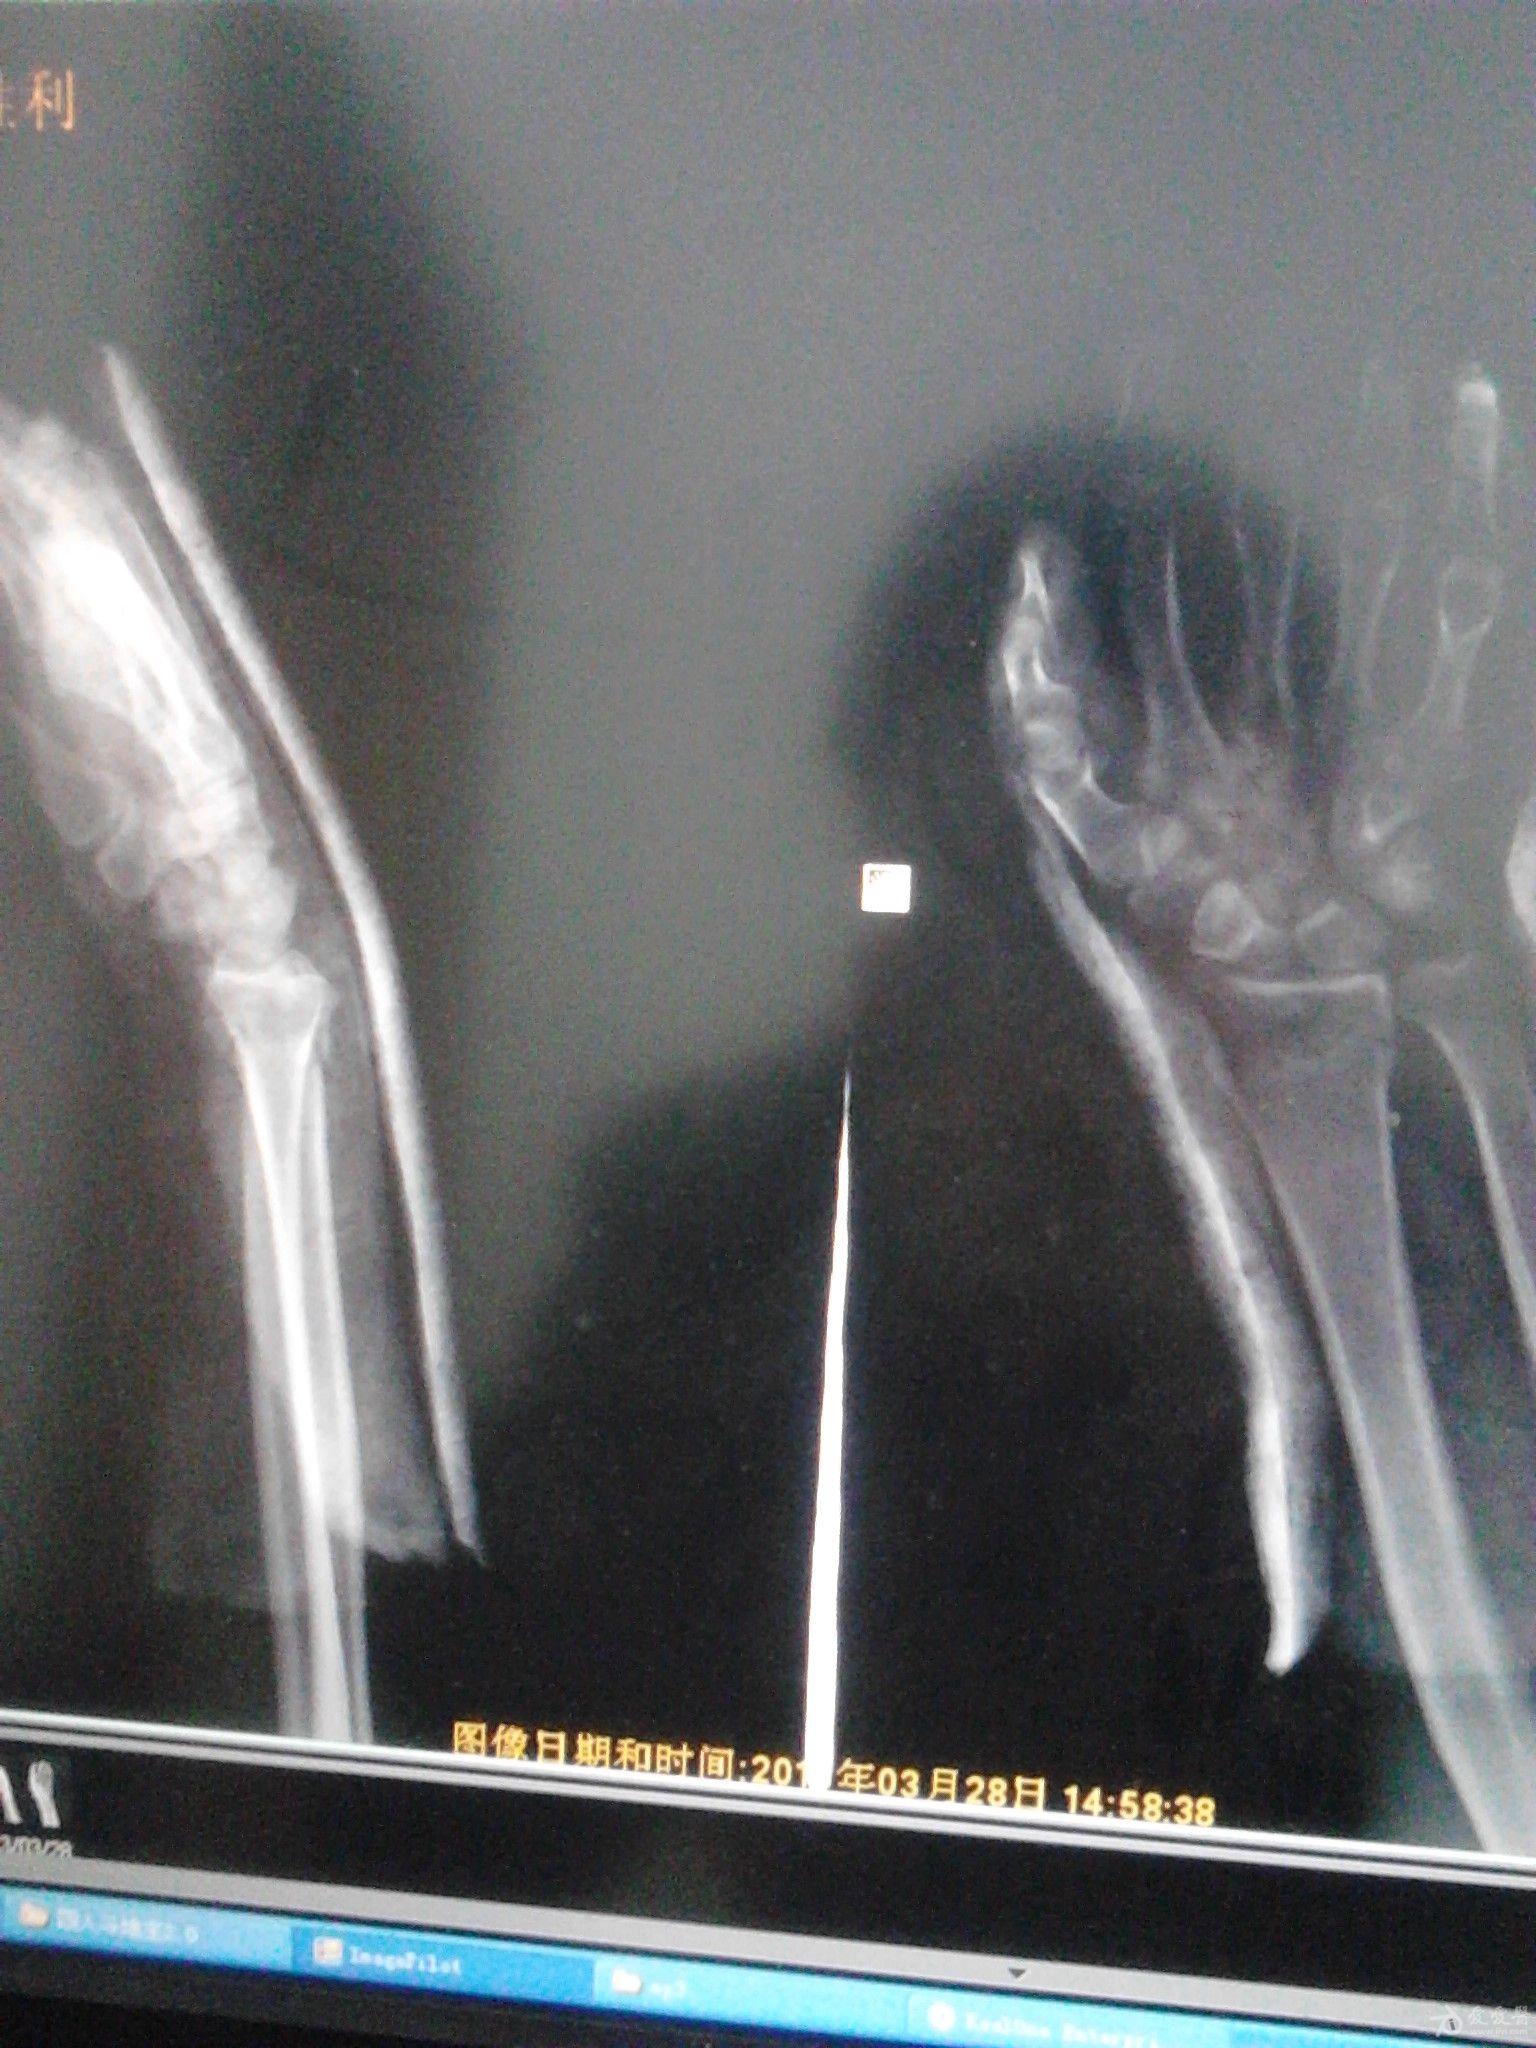

左陈旧性colles骨折一例

图片尺寸800x600